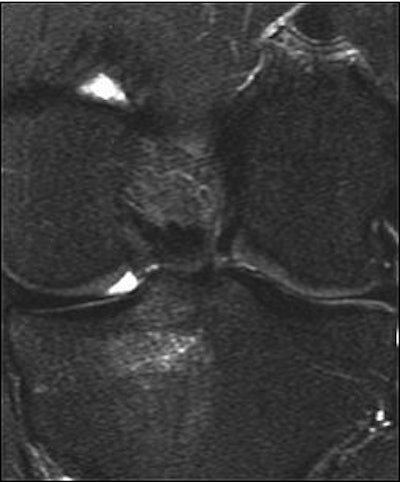

![]() |

| A 31-year-old man with fast resolution of bone bruise, reticular lesion type. Coronal T2-weighted fast-suppressed images (TR/TE, 12/3,700; fat saturation; section thickness, 3 mm; field-of-view, 180 x 135 mm; matrix, 385 x 224) show fast resolution of bone bruise from baseline (above), to three-week follow-up (middle), and at nine-week follow-up (below). |